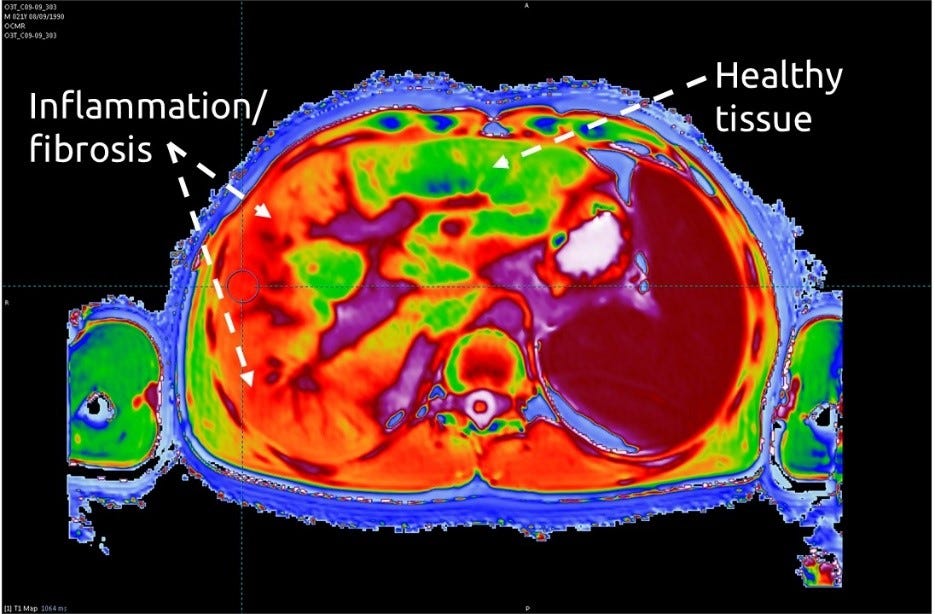

From axisimagingnews.com

Diagnosing Autoimmune Hepatitis Via Imaging Axis Imaging News Autoimmune Hepatitis Liver Mri Citation, doi, disclosures and article data. Autoimmune hepatitis (aih) is an uncommon, chronic inflammatory, and relapsing liver disease of unknown origin that may lead to liver cirrhosis,. Imaging has also a role in excluding overlapping syndromes. Autoimmune hepatitides) is a rare type of chronic. Two abdominal radiologists, blinded to pathology data, reviewed the mri examinations of 20 patients with autoimmune. Autoimmune Hepatitis Liver Mri.

From liverline.com

Multiparametric Resonance Imaging (MRI) as a Safe, Non Autoimmune Hepatitis Liver Mri Citation, doi, disclosures and article data. Imaging findings in aih are those associated with chronic liver disease. To retrospectively evaluate the morphologic and enhancement features of the liver on magnetic resonance (mr) images obtained in. Autoimmune hepatitis (aih) is a chronic inflammatory liver disease of unknown origin that can lead to liver cirrhosis, hepatocellular carcinoma (hcc), liver transplantation or death.. Autoimmune Hepatitis Liver Mri.